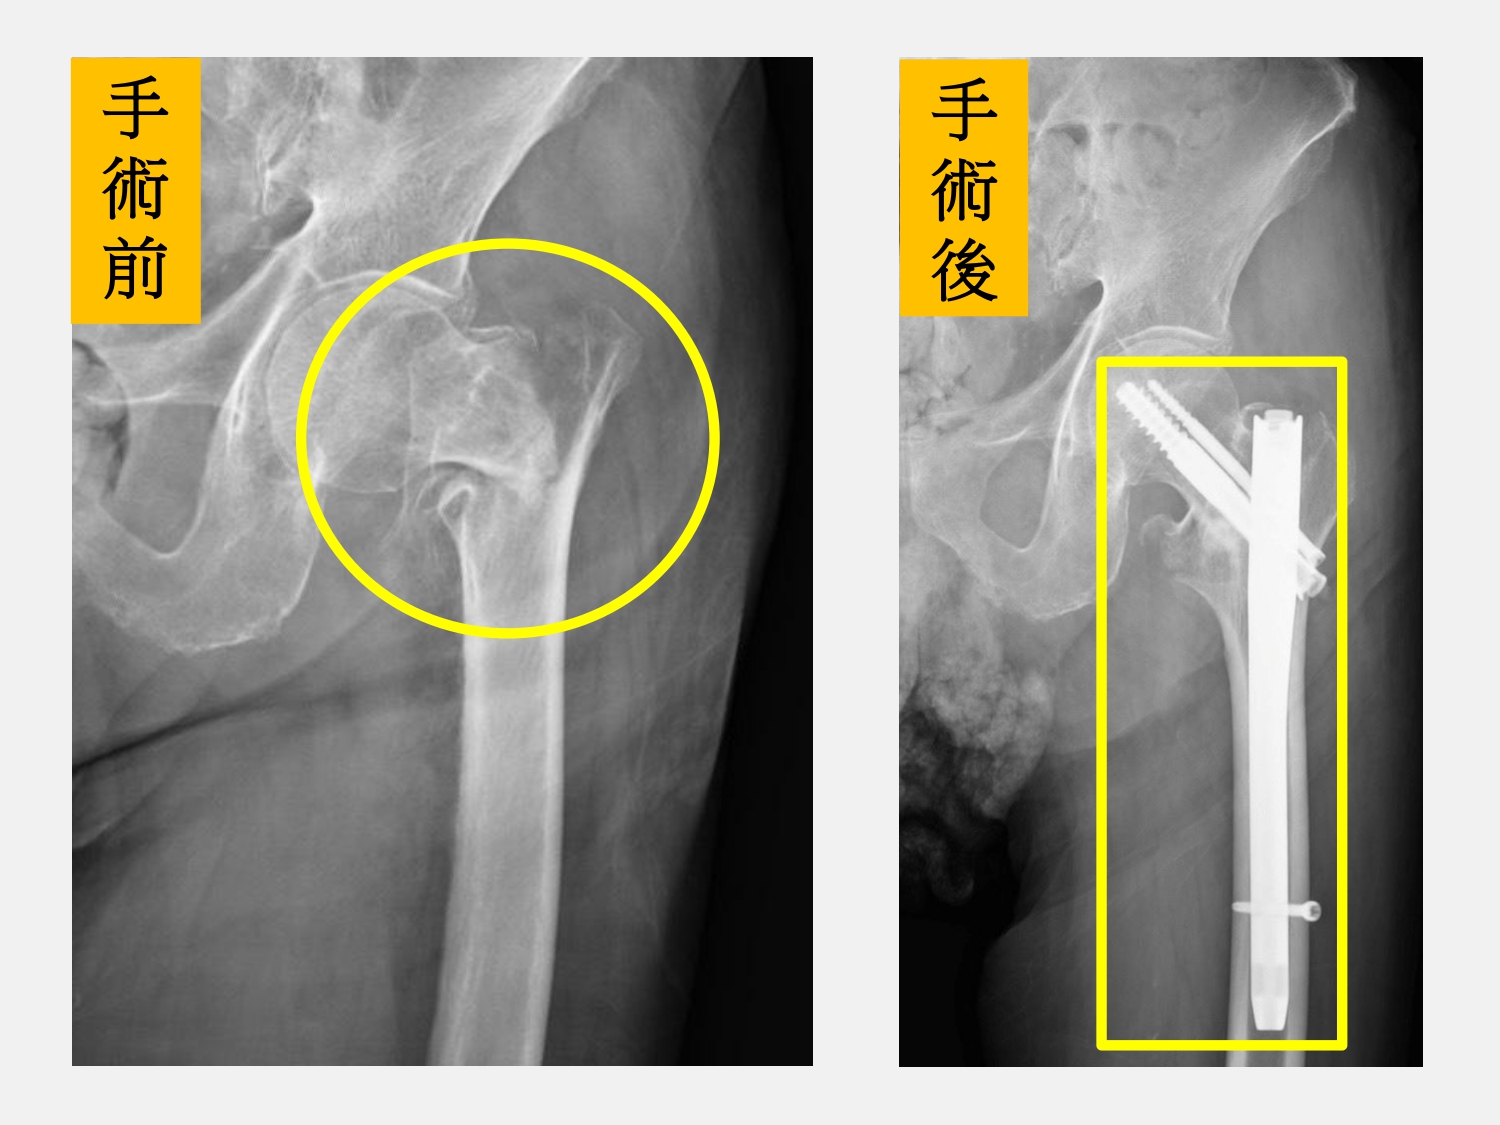

91歲當「阿祖」的陳老先生有糖尿病、高血壓和胃潰瘍,長期都在仁愛長庚合作聯盟醫院(大里仁愛醫院)定期追蹤治療。某日中午,從小疼愛的孫子帶著曾孫回台中來探望陳老先生,喜出望外的他要下樓開門時卻不小心踩空跌了下來,左邊髖關節非常的疼痛完全無法動彈,家屬連忙叫救護車送到該院急診,照了X光發現是左邊的髖關節粉碎性骨折,在骨科部黃贊文部長的安排下順利完成骨折固定手術。陳老先生在手術後除了接受骨質疏鬆症的治療和急性後期整合團隊照護外,還有中醫團隊加入,藉由整合中西醫的優勢一同照護,2週後順利出院,享受天倫之樂。